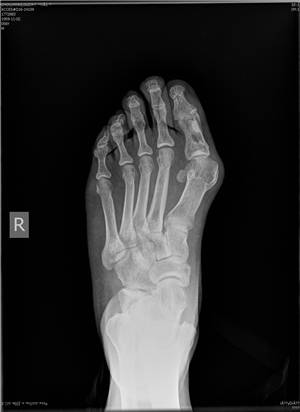

传统方法(左)与微创矫形方法(右)对比

微创矫形方法术前(左)术后(右)X光对比